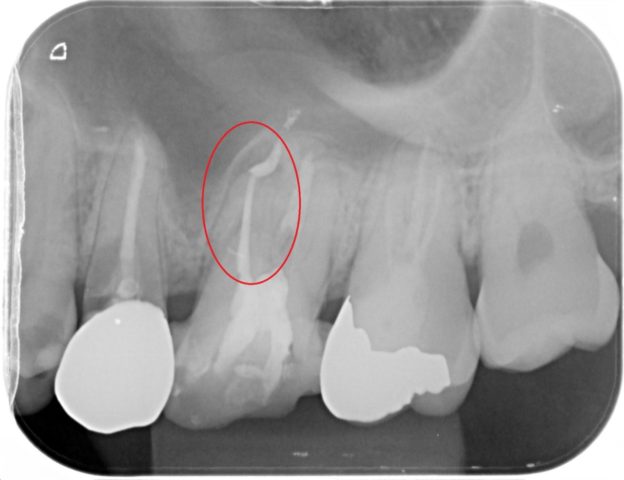

神経をすでに取っている歯だったため、痛みはありませんでしたが、根の治療が不十分でお薬が入っていない根があったため再治療を行いました。

全部治療して綺麗にしたい!とのことでしたので、全体的な治療を行いました。

その結果、セラミックを用いた被せ物を作製したことで見た目もとても綺麗になりましたし、汚れがつきにくく虫歯になりにくい歯にすることができました!